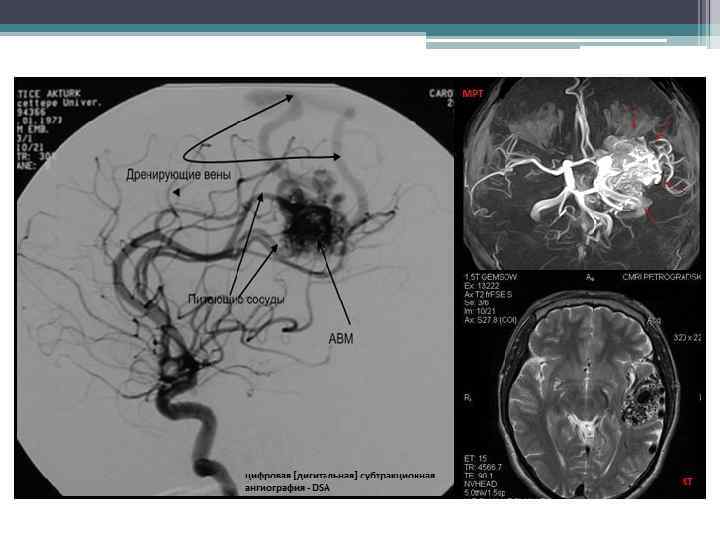

Артериовенозные мальформации (АВМ) • представляют собой неправильное соединение артериальных и венозных сосудов, формирующих ядро, минуя капиллярную сеть. В АВМ большого размера питающих сосудов может быть несколько, причем некоторые из них могут быть со стороны противоположного полушария. В теле АВМ количество сосудов артериального типа невелико, значительно превалируют сосуды, которые обозначают как диспластические. Дренирующие вены могут быть поверхностными и глубокими, причем если отток происходит в глубокие вены, то риск кровоизлияния выше, чем при оттоке в поверхностные вены. Описаны три основных анатомических варианта строения ядра АВМ

Диагностика: АВМ головного мозга проявляются характерными признаками по данным МРТ характеризуется высокой чувствительностью в выявлении АВМ, при этом может иметь место пустотный сигнал в Т 1 и Т 2 режимах, часто со следами гемосидерина. КТ обладает низкой чувствительностью в выявлении АВМ, однако КТ -ангиография высоко информативна. Ангиография является золотым стандартом в выявлении артериальной и венозной анатомии АВМ. При АВМ головного мозга специфичных изменений лабораторных показателей нет.